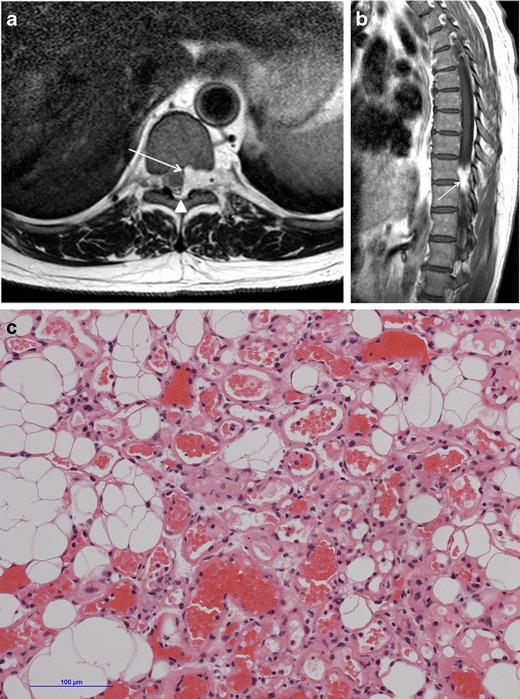

Haemangiomas of the vertebrae, usually regarded as having little or no consequence, may display aggressive features, including extension into the extradural space, and cause significant neurological symptoms and signs necessitating treatment. Extraosseous haemangiomas in an extradural or intradural extramedullary location are a rare entity. Here we review our radiologic and pathologic experience of osseous haemangiomas with extradural extension and primary extradural and intradural extramedullary haemangiomas. Magnetic resonance imaging plays a pivotal role in the characterisation of spinal haemangiomas, with typical imaging features including T1 and T2 signal hyperintensity. Atypical and aggressive imaging features are also described. Spinal angiography may be required to differentiate haemangiomas from non-vascular lesions. This is a rare and unusual entity, and should be considered as a differential diagnosis for some extramedullary masses.

椎骨血管瘤通常被认为影响不大或无影响,但可能呈现侵袭性特征,包括延伸至硬膜外间隙,并导致严重的神经症状和体征,需要进行治疗。硬膜外或硬膜内髓外位置的骨外血管瘤是一种罕见的实体。在此,我们回顾了骨血管瘤伴硬膜外延伸以及原发性硬膜外和硬膜内髓外血管瘤的放射学和病理学经验。磁共振成像在脊柱血管瘤的特征性诊断中起关键作用,典型的成像特征包括T1和T2信号高增强。还描述了非典型和侵袭性成像特征。可能需要进行脊髓血管造影以区分血管瘤与非血管性病变。这是一种罕见且不寻常的实体,应被视为某些髓外肿块的鉴别诊断。